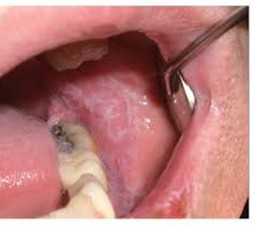

Q166. A patient presents with the following lesions and has burning sensations on eating spicy food. Which of the following drugs is responsible here?

- Lithium

- Beta blockers

- Fluconazole

- Ciprofloxacin

Answer: A